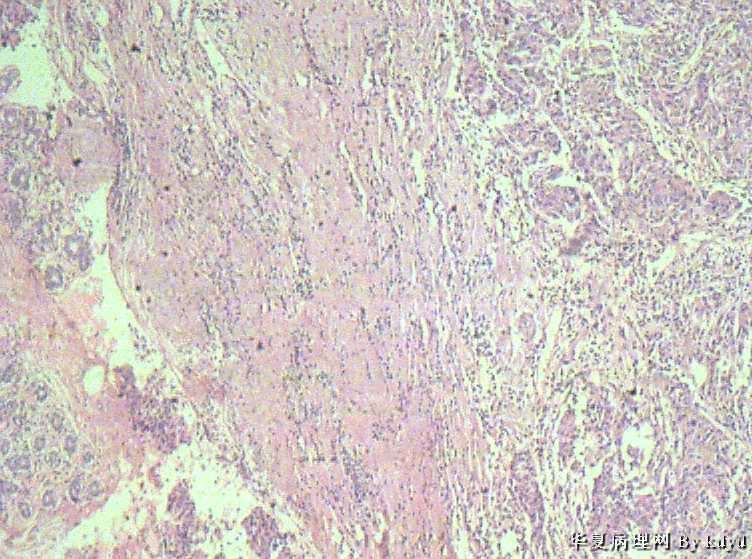

B3997左乳肿瘤--浸润性导管癌?

37岁,女。左侧乳腺肿块发现5个多月,伴隐痛。

手术见:肿块与周围组织分界不清,无明显包膜。

大体:不整形组织大小约3.5*35*2CM,未见明显包膜。质较软,切面浅黄色,一侧见一小囊腔直径约0.8CM囊壁较粗糙。

• 左乳肿瘤--浸润性导管癌?图3

图3

标签:乳腺浸润性导管癌 原位癌

浸润性乳腺导管癌?

IDC

乳腺浸润性导管癌

浸润性导管癌

应该是个浸润性导管癌

诊断乳腺浸润性导管癌确实有些担心,制片质量确实要提高,制作优良的切片,是正确诊断的前提。